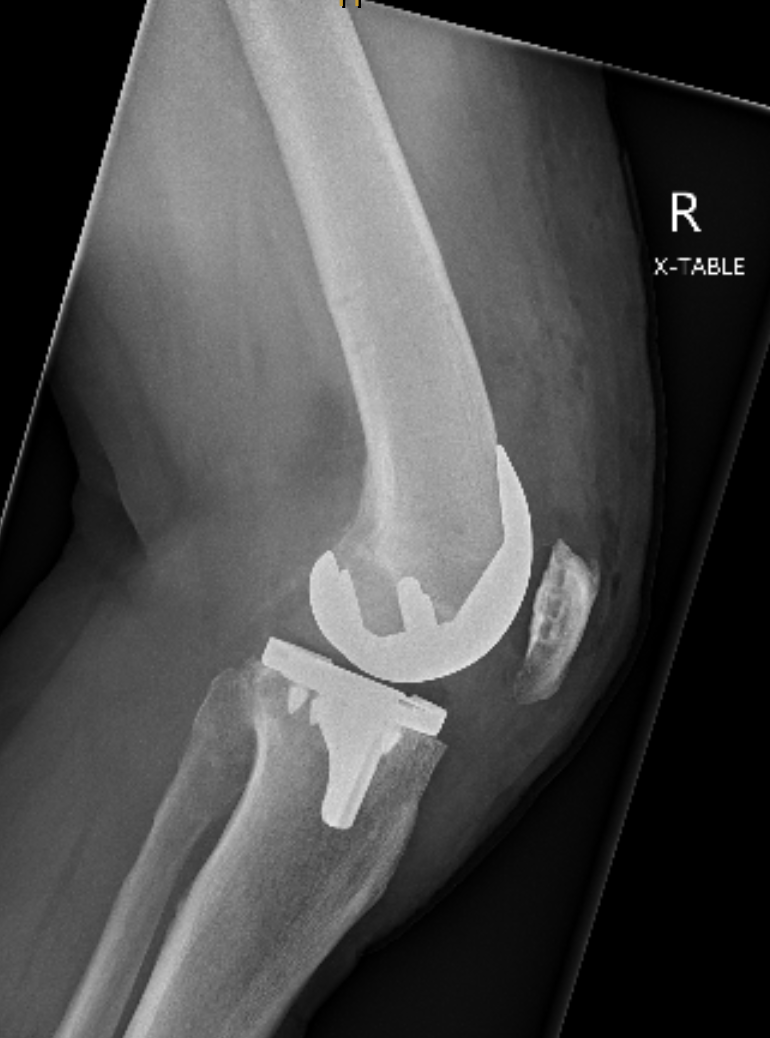

Knee Replacement

A knee replacement removes the worn cartilage and damaged joint surfaces of the knee and replaces them with smooth, durable artificial components. The new metal and plastic surfaces are designed to glide comfortably and restore stable movement.

It is considered when pain, stiffness, or loss of function from arthritis or certain knee injuries affects daily activities and non-surgical treatments are no longer providing relief.

The aims are to reduce pain, improve walking and knee function, and restore day-to-day comfort.

Modern knee implants provide reliable long-term performance. About 90 to 95 percent function well at 15 years, with durability affected by age, activity levels, and overall health.